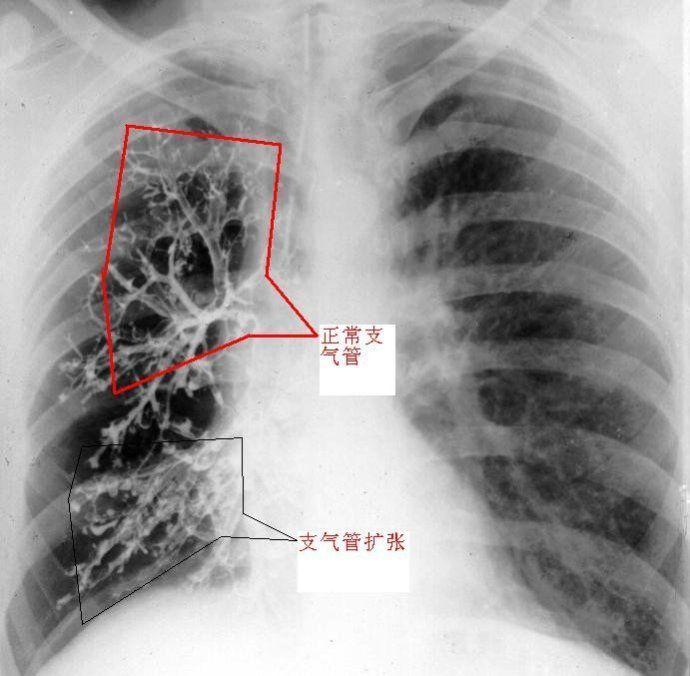

【支气管扩张症胸部x线检查的表现】【图】支